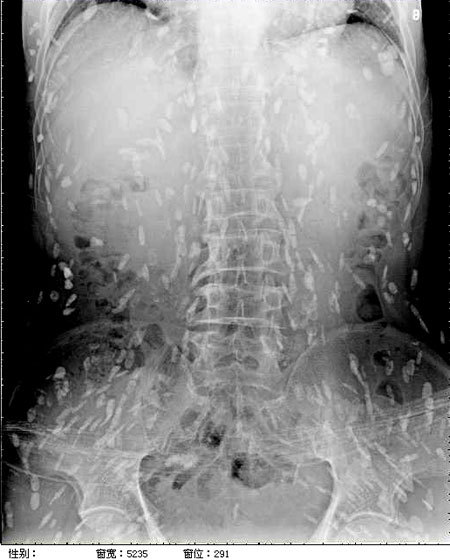

광둥성 푸산시 순더 지역에서 한 남성은 회를 섭취한 뒤, 복부 통증과 피부 가려움증 증상을 겪었습니다. 이로 인해 그는 난팡 의과대학 부속병원을 찾아 진료를 받았습니다. 의사는 이 환자의 증상을 확인하기 위해 엑스레이를 촬영하였고, 이 사진에서는 그의 온몸에 기생충이 퍼져 있는 것을 확인할 수 있었습니다. 이러한 기생충은 촌충 또는 열두 조충이라고 불리는 벌레로서, 사람의 장내에서 기생하는 것으로 알려져 있습니다.